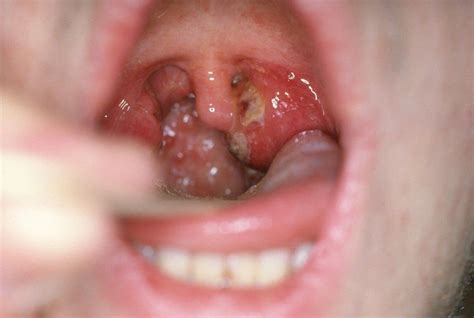

Ulcers in the throat, also known as throat ulcers or aphthous ulcers, are a common condition that can cause significant discomfort and pain. These ulcers are typically small, round, or oval-shaped sores that develop on the mucous membranes of the throat. They can vary in size and number, and while they are usually not serious, they can be quite bothersome. Understanding the causes, symptoms, and treatment options for ulcers in the throat is essential for managing this condition effectively.

• Redness and Swelling: The affected area may appear red and swollen.

• White or Yellow Coating: Some ulcers may have a white or yellow coating.

• Difficulty Swallowing: Severe ulcers can make it difficult to swallow food and liquids.

Throat Ulcers Ulcers that develop on the mucous membranes of the throat, often accompanied by pain and swelling. Bacterial, viral, or fungal infections, trauma, and autoimmune disorders.

• pictures of ulcers in throat